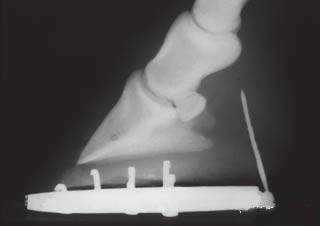

看下面一个被钉子扎伤的蹄。这个钉子好像也没有长的有什么神奇,或者天赋异禀。

我们看不出它是否会伤及关键结构。于是兽医就给拍了一张X光片。

当我们看到这张X光片,会惊叹原来钉子有这么长呀。好惊险,它不会对骨骼造成损伤,但进入的深度和角度好像可能会伤及腱鞘。于是兽医又做了一张损伤区域对比造影。

通过这张造影图,兽医确定这根钉子没有造成腱鞘的损伤。虽然钉伤导致马匹跛行,但好在没有伤及重要结构,所以这匹马的钉伤还是好治疗的。

所以当发现马匹被硬物扎伤的话,请尽快联络兽医,兽医可以通过插入的部位、角度、X光片等手段判断出是否伤及关键部位。但如果你手欠给它拔出来了,兽医可能不好确定了。